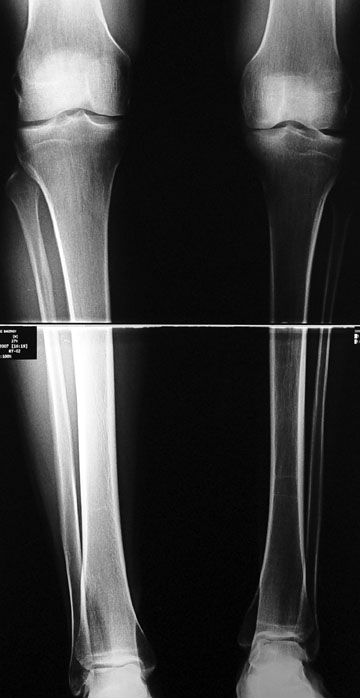

3- POSTTRAVMATİK BACAK KISALIĞI (YANLIŞ KAYNAMA)

Bu Bacak Kısalık tipi bir kırığın kısalmış pozisyonda kaynaması ile oluşur. Bir çok vaka yetişkinlerde görülür ve sadece bir uzatma ile tedavi edilebilir. Ek deformiteler de aynı anda düzeltilebilir. Bu hastaların çoğu çivi üzerinden uzatma veya tam implante edilen çivi ile tedavi edilebilirler.